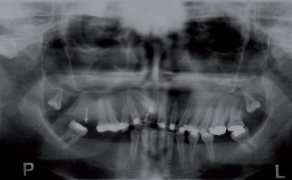

Asymetryczna ekspansja szczęki z użyciem zmodyfikowanego aparatu Quad Helix w leczeniu izolowanego zgryzu krzyżowego

Streszczenie: Jednostronny zgryz krzyżowy tylny często obejmuje tylko jeden ząb, przeważnie pierwszy ząb trzonowy górny; w takich przypadkach uzyskanie asymetrycznego ruchu zęba trzonowego nigdy nie jest łatwe, dlatego, aby uniknąć nadmiernej ekspansji łuku szczęki, konieczne jest odpowiednie zaprojektowanie aparatu ortodontycznego wraz z zakotwieniem. Dzięki swojej prostocie i skuteczności opisany zmodyfikowany aparat Quad Helix stanowi ważne narzędzie terapeutyczne w przypadku izolowanego zgryzu krzyżowego tylnego.

Zgryz krzyżowy tylny jest wadą zgryzu często spotykaną w praktyce ortodontycznej. Ta nieprawidłowość bywa częścią szerszego zespołu zaburzeń ortodontycznych, ale może również stanowić izolowany defekt, obejmujący tylko jeden ząb.

Według różnych badań częstość występowania zgryzu krzyżowego tylnego waha się między 6% a 23%. Najczęściej spotykany jest jednostronny zgryz krzyżowy tylny, około 6-7% przypadków, w porównaniu z obustronnym występującym w ok. 1,5-3,5% przypadków [1, 2].

Etiologia zgryzu krzyżowego tylnego obejmuje czynniki genetyczne, środowiskowe i czynnościowe oraz nawyki [3, 4]. Jednostronny zgryz krzyżowy tylny może być zdefiniowany jako czynnościowy lub prawdziwy. Prawdziwy jednostronny zgryz [...]